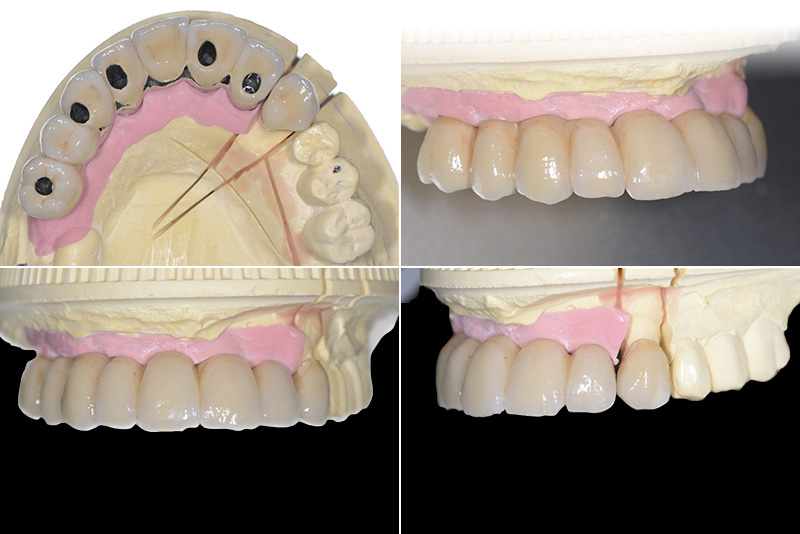

Vengono utilizzati 2 tipi di provvisori: il primo, cementato ai denti vicini, viene utilizzato dal momento dell’estrazione del dente fino ad impianto osteointegrato (circa 6 mesi); il secondo, avvitato direttamente all’impianto, ha una funzione di prova estetica ma soprattutto di guida per la maturazione dei tessuti gengivali peri-implantari portandoli verso la maturazione completa prima di posizionare la corona finale in disilicato di litio.